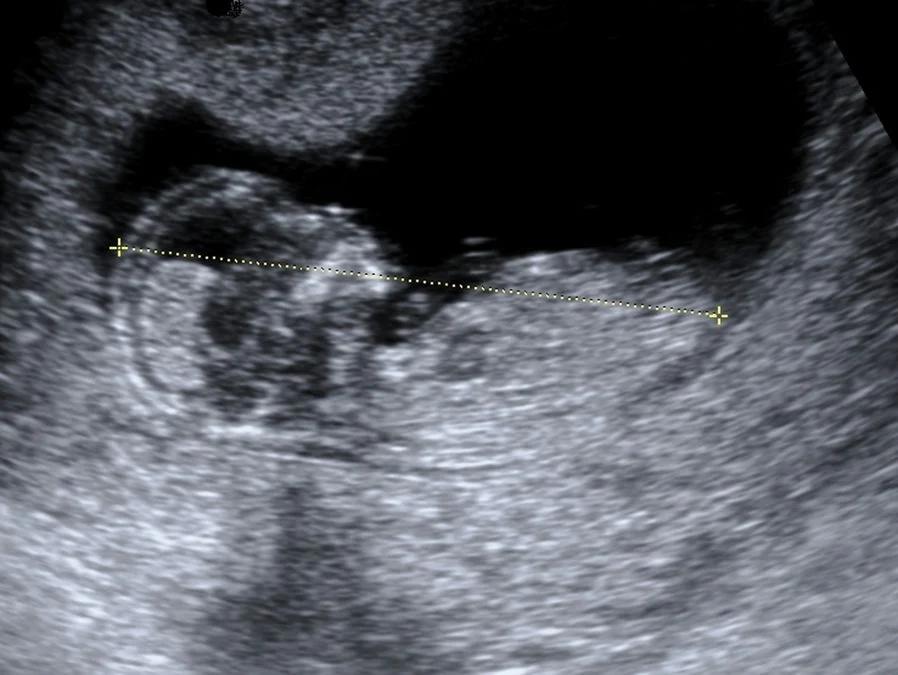

Die SSL ist die Distanz vom höchsten Punkt des Kopfes (Scheitel) bis zum Steissbein des Embryos. Diese Messung ist besonders wichtig in der frühen Schwangerschaft, da es aufgrund der gekrümmten Haltung des Embryos mit angezogenen Beinen und gesenktem Kopf schwierig ist, die gesamte Länge des Embryos zu messen. Die SSL ermöglicht es den Ärzten, die Grösse und Entwicklung des Embryos genau zu beurteilen.

Die SSL wird mit Hilfe eines Ultraschallgeräts gemessen. Die Ärztin oder der Arzt markiert auf dem Bildschirm den höchsten Punkt des Kopfes und das Steissbein des Embryos. Das Ultraschallgerät berechnet dann die Distanz zwischen diesen beiden Punkten in Millimetern.